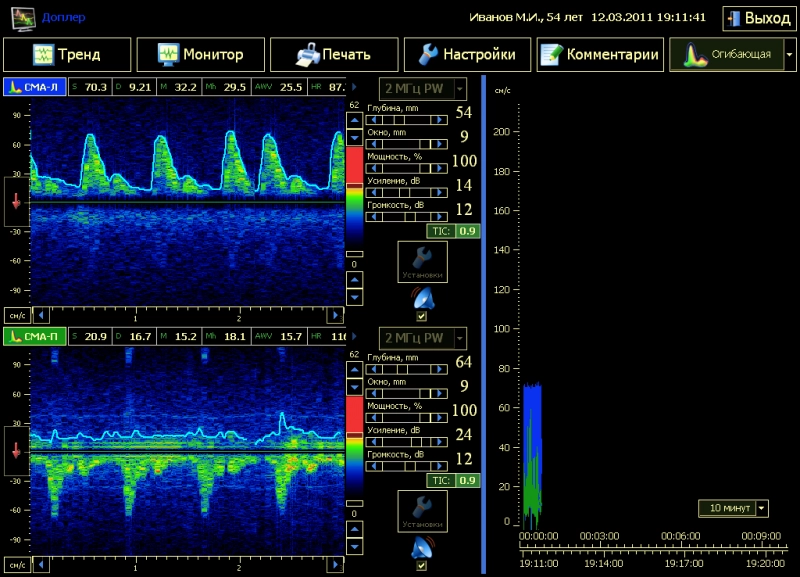

Первой разработкой нового поколения средств экспресс - диагностики ССС ЛДС, доведённой до уровня опытного образца стала отечественная система “Unimonex” (ООО «БИОСОФТ-М», г.Зеленоград). “Unimonex” - система многоканальных on-line мониторинговых исследований состояния ССС одновременно несколькими методиками с расширенными возможностями по обработке, визуализации и хранению результатов диагностики. Система комплектуется следующими модулями: ультразвуковым допплерографом для исследования церебральной и периферической гемодинамики, электроэнцефалографом для исследований биоэлектрической активности головного мозга, электрокардиографом для исследований электрической активности сердца, пульсоксиметром для исследования насыщения гемоглобина крови кислородом, капнографом для исследования концентрации углекислого газа в выдыхаемом воздухе, тонометром для исследования артериального давления. Каждый модуль регистрирует в режиме реального времени набор клинически-значимых для оценки нарушений ССС параметров её состояния. Все измерительные каналы функционируют одновременно и строго синхронизированы за счёт реализации уникальных аппаратно-программных решений. Дисфункции ССС отражаются одновременно в клинических показателях нескольких методик, что позволяет оперативно локализовать заболевание и достоверно его диагностировать. В результате, обеспечивается высокая эффективность лечения. Регистрация и обработка данных о состоянии ССС по каждому из измерительных каналов комплекса осуществляется в следующей последовательности: -с датчиков соответствующего канала снимается сигнал с характеристиками, определенными для выбранного метода исследования физиологических параметров пациента; - аналоговый сигнал с датчика поступает в специализированный приборный модуль, выполняющий аналого-цифровое преобразование сигнала и его первичную обработку (фильтрация, усиление и т.д. ); - оцифрованные данные каждого канала поступают в вычислительный модуль комплекса, где выполняется синхронизация данных, их обработка, визуализация и запись в БД. На рис 1. показано рабочее окно программы в момент регистрации параметров ССС ЛДС.

Рис. 1. Рабочее окно системы мультимодальных обследований ССС ЛДС

В правой части окна отображаются графики регистрируемых параметров, а в левой - расчетные индексы. Индексы и графики соответствуют одной и той же методике исследования и отделены на экране горизонтальными линиями. Таким образом, последовательно «сверху - вниз» на рабочем экране “Unimonex” располагаются области индикации результатов совместно используемых методик. Количество интегрируемых методик и их назначение определяется клиническими аспектами проводимых исследований и может варьироваться в широких пределах. Unimonex» позволяет синхронизировать специальными техническими и программными средствами регистрируемые при обследовании потоки данных, представленные в различных форматах, в единую систему комплексного анализа и обработки диагностической информации о состоянии ССС ЛДС. Комплекс имеет развитые средства настройки состава и количества используемых при обследовании методик. Выбор совместно используемых методик определяется задачами клинических исследований конкретного вида патологии. Визуализация данных каждого из каналов диагностики имеет два формата представления: сжатый и развёрнутый. Первый, используется для отображения информации одновременно по всем каналам диагностики, второй – для детализации результатов исследований в рамках конкретной методики. Сжатый формат представления данных имеет следующую структуру: в левой части канала отображается информационная панель с расчетными индексами, в правой части - график регистрируемого сигнала или тренд расчётного индекса. Такая форма представления наиболее эффективна для визуального восприятия и анализа нескольких потоков информации и хорошо зарекомендовала себя на практике. Информационная панель одновременно с индикацией выполняет функцию управления форматами представления данных каждой методики. Если активировать (щелчком мыши, с клавиатуры, касанием сенсорного монитора) область панели, отвечающей за отображение параметров конкретной методики, то будет открыт развёрнутый формат представления сигналов и результатов их обработки в рамках выбранной методики. Например, если выбрать область индикации расчетных параметров церебральной гемодинамики (рис.2), то на экран монитора будет выведен развёрнутый формат представления результатов ультразвуковой допплерографии исследуемых сосудов (рис.3).

Рис.3. Рабочее окно допплерографической методики исследования